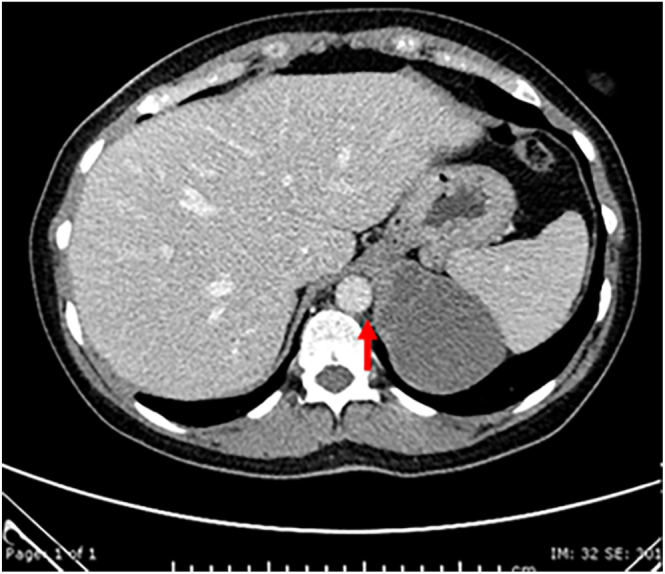

Summary: Bronchogenic cysts, developmental malformations of the primitive foregut, extremely rarely occur in the retroperitoneum. Here, we present a retroperitoneal bronchogenic cyst presenting as an adrenal incidentaloma and masquerading clinically as a phaeochromocytoma.

Learning points: Retroperitoneal bronchogenic cysts are exceptionally rare, particularly presenting as adrenal incidentalomas (AI), and can mimic other conditions such as non-functioning phaeochromocytomas. This case emphasises the need to consider rare conditions such as retroperitoneal bronchogenic cysts in the differential diagnosis of AI, especially when imaging findings are unusual despite normal hormonal studies. Atypical adrenal masses still warrant surgical evaluation and histopathological analysis to confirm the diagnosis and exclude rare entities. The occurrence of retroperitoneal bronchogenic cysts highlights the importance of understanding embryogenesis, particularly the migration pathways and foregut development. Histopathological examination remains crucial for diagnosing bronchogenic cysts, as they demonstrate the characteristic ciliated columnar epithelium with subepithelial smooth muscle, seromucinous glands, and cartilage.